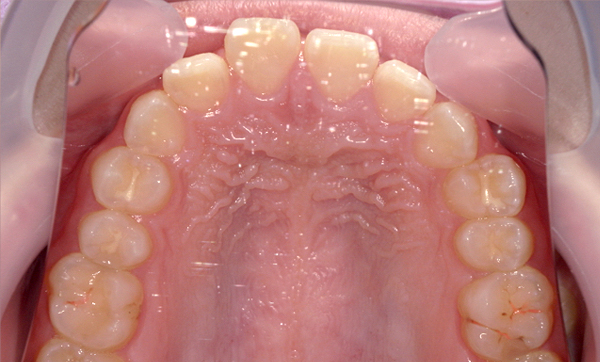

| 治療前 | 治療後 |

|---|---|

|